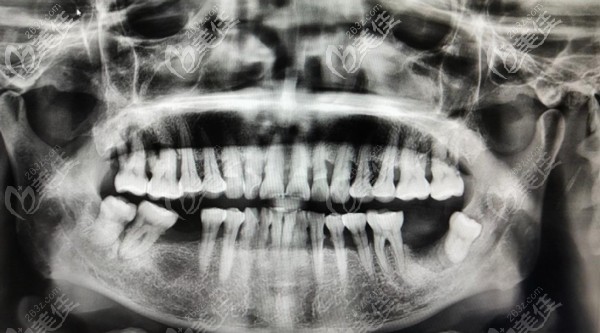

术前照片:

我的父亲今年60岁,打我记事起一直从事的是建筑行业,所以有长期吸烟的习惯,自去年开始他的牙齿慢慢开始松动甚至开始脱落,后来到口腔医院检查才知道是常年吸烟导致的牙龈萎缩继而引起的满口牙松动。